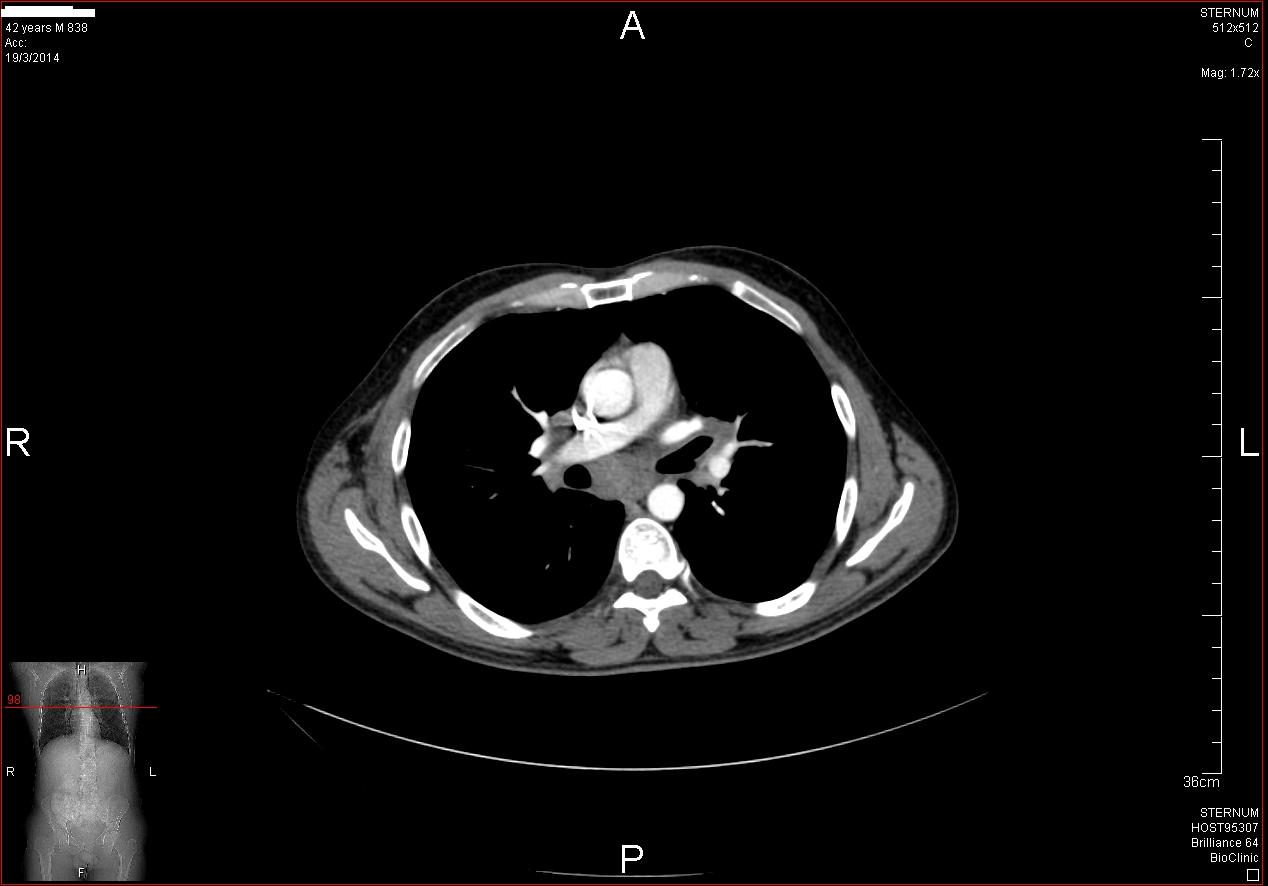

Άνδρας 43 ετών, χωρίς προηγούμενο ατομικό ή οικογενειακό ιστορικό, εμφάνισε επίμονους εμέτους και επιγαστραλγία. Υποβλήθηκε σε αξονική τομογραφία θώρακος, άνω και κάτω κοιλίας από το θεράποντα ιατρό του που έδειξε διάχυτη θωρακική και κοιλιακή λεμφαδενοπάθεια, με διογκωμένους λεμφαδένες στον υποτροπιδικό χώρο, στον αλλήρειο τρίποδα, στον ηπατοδωδεκαδακτυλικό σύνδεσμο και πέριξ του παγκρέατος. Ο ασθενής παραπέμφθηκε για ενδοσκοπικό υπέρηχο και λήψη βιοψιών από τους λεμφαδένες. Έγινε βιοψία με ειδική βελόνα για λήψη ιστοτεμαχίων (Pro-Core 19g) από λεμφαδένες σε 3 διαφορετικές θέσεις (υποτροπιδικά, αλληρείου τρίποδα και ηπατοδωδεκαδακτυλικού συνδέσμου). Η ιστολογική εξέταση και ο ανοσοϊστοχημικός έλεγχος έδειξε αδενοκαρκίνωμα χαμηλής διαφοροποίησης χωρίς θετικότητα στις επιμέρους, ειδικές χρώσεις. Ο ενδοσκοπικός έλεγχος του πεπτικού επιβεβαίωσε την ύπαρξη νεο-εξεργασίας στην ηπατική καμπή του παχέος εντέρου που ιστολογικά ήταν ένα αδενοκαρκίνωμα χαμηλής διαφοροποίησης. Ο ασθενής παραπέμφθηκε για προεγχειρητική χημειοθεραπεία και χειρουργική αντιμετώπιση.

CT: υποτροπιδικός λεμφαδένας

CT: λεμφαδένας αλληρείου τρίποδα

CT: λεμφαδένας ηπατοδωδεκαδακτυλικού συνδέσμουνδεσμο

Βιοψία υποτροπιδικός λεμφαδένας (EUS-FNA)